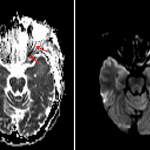

- Restricted diffusion involving the orbital and canalicular segments of the left optic nerve

Restricted diffusion involving the orbital and canalicular segments of the left optic nerve concerning for infectious involvement and/or infarct.